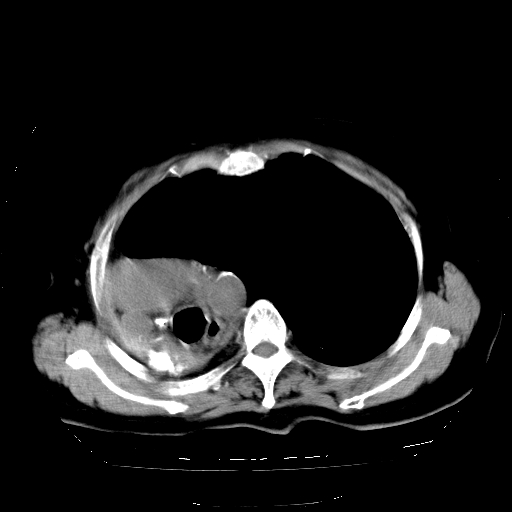

标题: CT23991:女,72岁,咳嗽、憋气一周。 [打印本页]

女,72岁,咳嗽、憋气一周,十年前曾患肺结核及胸膜结核。

1.右侧损毁肺伴胸膜钙化,2.左肺小结节灶,良性可能大,注意复查。3.肝脏左叶囊肿。4.先天性一侧肺不发育待出外(右侧胸廓无明显塌陷)。对比原片应该非常有帮助。

支持楼上,肝脏多发囊肿